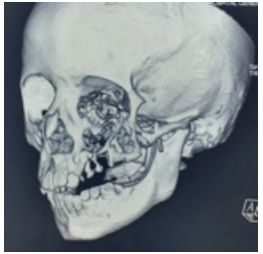

Paciente femenina de 8 años de edad, recibida en el mes de octubre de 2016, asintomática, sin antecedentes patológicos, alérgicos y quirúrgicos. Intraoralmente, presenta una masa tumoral de aproximadamente 6 x 6 cm a expensas de maxilar, que desplaza el primer molar y los molares temporales superiores izquierdos, no álgica a la manipulación (figura 1). En TAC contrastada se observa una lesión mixta de características osteolíticas, que involucra el seno maxilar, el reborde infraorbitario izquierdo y las celdillas etmoidales anteriores (figura 2, figura 3 y figura 4). Se realiza una biopsia incisional, obteniendo un diagnóstico de lesión central de células gigantes (figura 5). Se solicita estudio de niveles séricos de paratohormona y calcitonina, obteniéndose valores de laboratorios normales. Se inicia terapia esclerosante con triamcinolona, con aplicaciones semanales de 5ml de triamcinolona de 10mg con lidocaína 2% con epinefrina 1:100 000 UI (7). En enero de 2017, se presenta con dolor espontaneo e incremento exponencial de la lesión, causando deformidad hemifacial izquierda, obstruyendo en un 50 % la luz de la cavidad oral. Se interviene para escisión de lesión tumoral y curetaje, retirándose al 90% y se realiza además derivación de conducto parotídeo izquierdo. En marzo de 2017, acude a control con aumento de volumen intraoral nuevamente. Se informa a sus familiares sobre la existencia de otra terapéutica sustentada por diferentes publicaciones, para estas lesiones que no responden a los tratamientos con esteroides y a los quirúrgicos. Tras su aceptación se programa terapia antiangiogénica con interferón alfa 2ª vía subcutánea de 3 a 6 millones de UI semanales por 4 a 8 meses, iniciándolo a las 48h tras la cirugía (5). En abril, es reintervenida, sin complicaciones, para escisión quirúrgica de lesión central de células gigantes recidivante agresiva, y se inicia terapia con interferón alfa 2ª para reducción y esclerosis de tumor. Se solicita interconsulta a Servicio de Psicología a fin de mes, por datos de depresión. Se enfatiza esta relación con el medicamento, así como malestar general, astenia, somnolencia y afectación del estado general. El Servicio de Psicología diagnostica un estado depresivo leve, que no se considera indicativo para detener tratamiento con interferón alfa 2ª. En junio de 2017, se corrobora la esclerosis de la lesión a través de exploración con TAC de macizo facial, simple y contrastada. La paciente se encuentra sin datos de actividad tumoral, estado físico y psicológico en buenas condiciones, transcurridos 36 meses al día de hoy (figura 6 y figura 7).